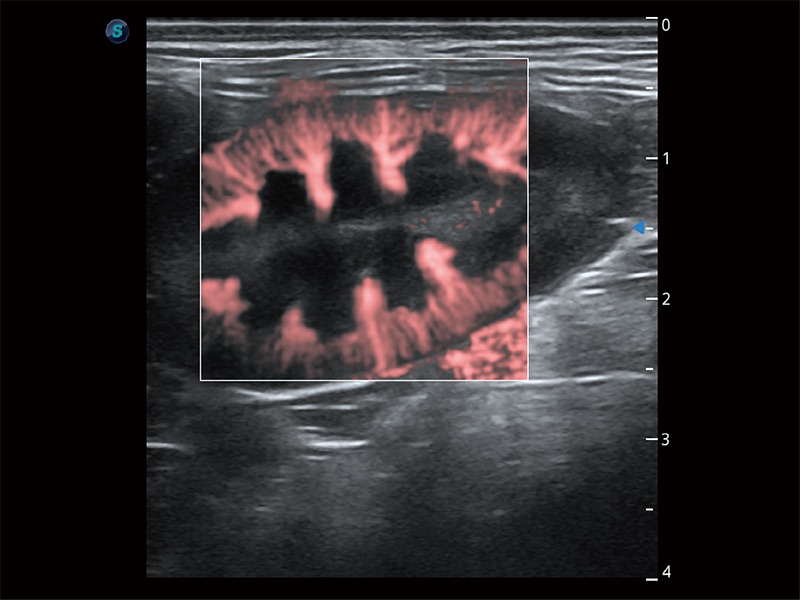

• Micro F 顯微血流成像

極大提升超低速微細(xì)血流的檢出能力,同時更精準(zhǔn)地濾除軟組織和超聲信號,為獸用醫(yī)生提供以往無法通過常規(guī)血流獲得的疾病診斷信息。

(犬)腸道

(犬)腎臟顯微血流